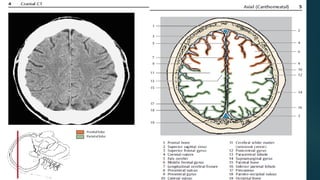

Este documento es el programa para un taller de imágenes del curso de emergencia 2015 impartido por el Dr. Víctor Delgado. El taller se centra en el uso de imágenes médicas para el diagnóstico y tratamiento de pacientes en coma traumático según la base de datos de Marshall. El Dr. Delgado es el único instructor repetido a lo largo del documento.